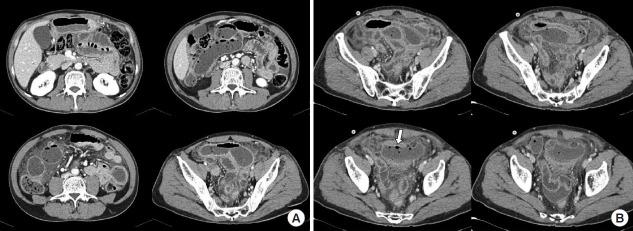

Paradoxical reactions to tuberculosis (TB) treatment are characterized by an initial improvement of the clinical symptoms followed by clinical or radiological deterioration of existing tuberculous lesions, or by development of new lesions. Intestinal perforation in gastrointestinal TB can occur as a paradoxical reaction to antitubercular therapy. A 55-year-old man visited the outpatient department with lower abdominal pain and weight loss. He was diagnosed with intestinal TB and started antitubercular therapy. After 3 months of antitubercular therapy, a colonoscopy revealed improvement of the disease. Three days after the colonoscopy, the patient visited the emergency room complaining of abdominal pain. Abdominal computed tomography revealed extraluminal air-filled spaces in the pelvic cavity. We diagnosed a small bowel perforation and performed an emergency laparotomy and a right hemicolectomy with small bowel resection. This report describes the case of intestinal perforation presenting as a paradoxical reaction to antitubercular and provides a brief literature review.

结核病(TB)治疗的矛盾反应表现为临床症状最初改善,随后现有结核病变出现临床或影像学恶化,或出现新病变。胃肠道结核中的肠穿孔可作为抗结核治疗的矛盾反应发生。一名55岁男性因下腹痛和体重减轻就诊于门诊。他被诊断为肠结核并开始抗结核治疗。抗结核治疗3个月后,结肠镜检查显示病情有所改善。结肠镜检查3天后,患者因腹痛前往急诊室。腹部计算机断层扫描显示盆腔腔内有腔外气体填充空间。我们诊断为小肠穿孔,并进行了急诊剖腹手术和右半结肠切除术及小肠切除术。本报告描述了作为抗结核治疗矛盾反应出现的肠穿孔病例,并提供了简要的文献综述。